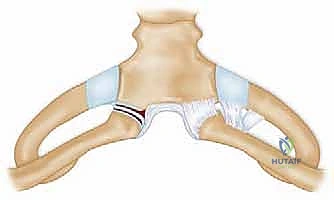

Modern stabilization relies on robust biological reconstruction. While primary repair of the capsule using suture anchors in the manubrium can augment the construct, a figure-of-eight graft reconstruction is the gold standard for restoring multiplanar stability. A semitendinosus or gracilis autograft (or allograft to minimize donor site morbidity) is preferred due to its length and tensile strength.

Drill holes, typically 4.0mm to 4.5mm in diameter, are meticulously created. In the medial clavicle, two holes are drilled from anterior to posterior, approximately 1 cm lateral to the articular margin and 1 cm apart. In the manubrium, two corresponding holes are drilled. Critical Step: When drilling the manubrium and the clavicle, a malleable retractor or a broad periosteal elevator must be placed deep to the bone to protect the mediastinal structures from the drill bit plunging. The drill must always be directed from anterior to posterior, with precise control.

The graft is then passed in a figure-of-eight configuration. Suture passing wires or curved shuttles are used to navigate the graft through the osseous tunnels. The graft is tensioned with the clavicle held in anatomical reduction (often requiring downward and posterior pressure on the medial clavicle). The graft limbs are then sutured to themselves and to the surrounding periosteal tissues using heavy, non-absorbable, braided sutures.